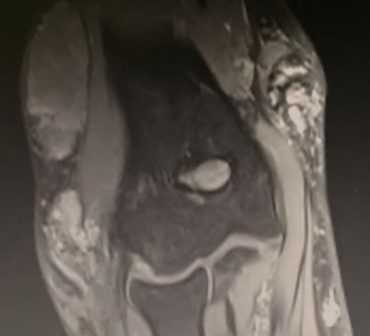

МРТ локтевого сустава в корональной плоскости. В подкожно-жировой клетчатке локтевого сустава отмечаются множественные образования неправильной вытянутой формы, местами сливающиеся между собой — вероятно, венозная мальформация.